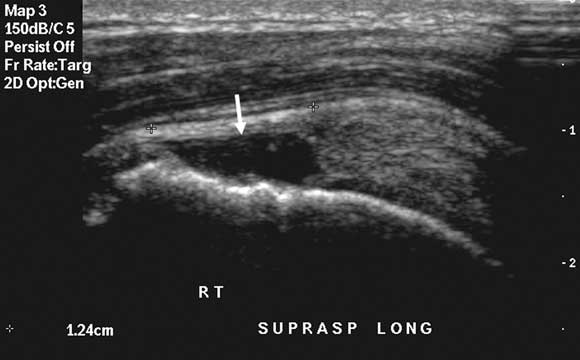

Case study 3 — shoulder impingement pain

A 35-year-old man with sudden worsening of deep shoulder impingement pain from doing upper body weights at the gym. Differential diagnosis: Rotator cuff tendinopathy is the most likely diagnosis. Shoulder instability is very common in younger athletes, but becomes less relevant in older athletes. Therefore, although a glenoid labral tear (associated with shoulder instability) remains possible, the diagnosis not to be missed is a full thickness rotator cuff tear (as surgical repair would probably be indicated at this age). Imaging options: If rotator cuff power remains strong, initial imaging may not be necessary, and a trial of physiotherapy may be justified. A single clinically-guided subacromial cortisone injection22 or topical glyceryl trinitrate therapy23 are also justified. If rotator cuff power is reduced, or first-line management fails, any cuff tear should be accurately characterised to determine the need for surgical intervention. The imaging options are ultrasound (Figure), MRI, or CT-arthrogram, and the choice will vary with local circumstances (eg, the preference of the shoulder surgeon, the skill set of the radiologist, the availability and affordability of MRI). A preliminary x-ray is also of definite value in assessing other factors (eg, acromial bone spurring, acromial morphology, acromioclavicular joint status) that might influence the surgical management. Both ultrasound and MRI would avoid invasive arthrography but may not always be locally available or reliable. Ultrasound is more useful in older patients, in whom glenoid labral tears are not a major concern, whereas MRI is preferred in younger patients, in whom underlying glenohumeral joint instability is an important consideration. A further advantage of ultrasound can be its ability to accurately guide an injection of subacromial cortisone, which may be the best management option if an initial clinically-guided injection has failed and there is no significant rotator cuff tear. |